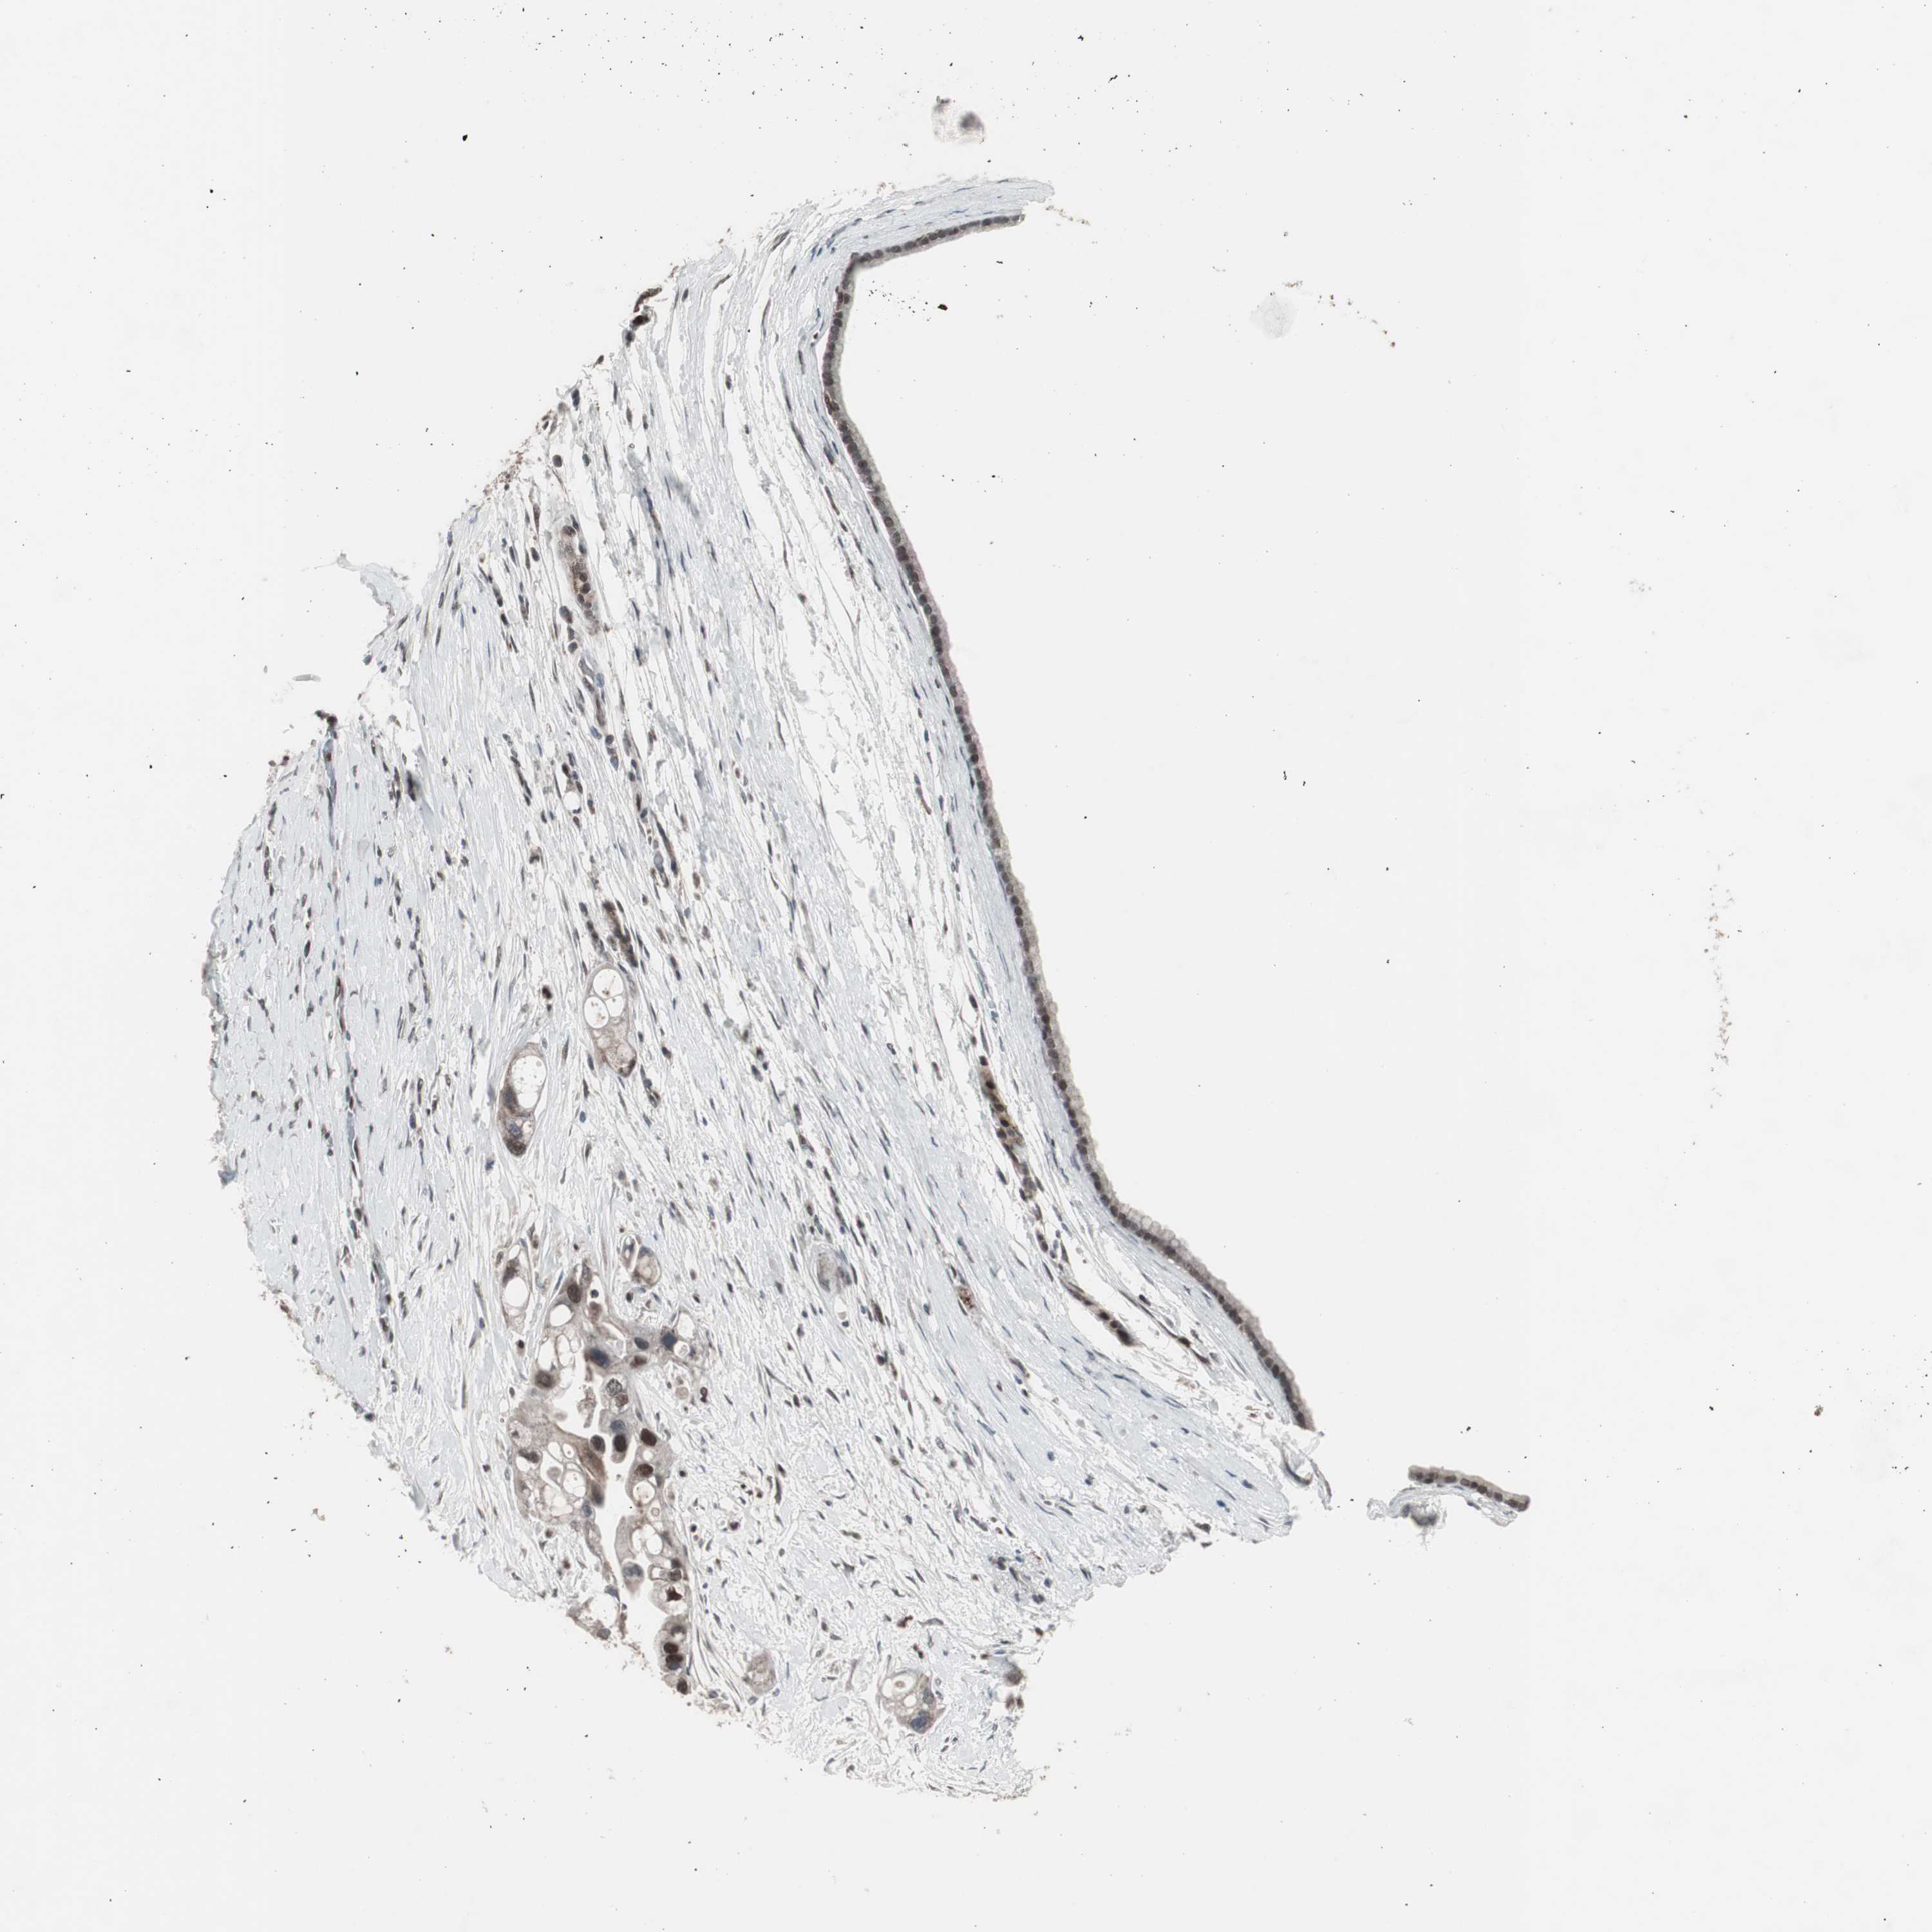

PANCREATIC CANCER - Protein expressioni

A mouse-over function shows sample information and annotation data. Click on an image to view it in a full screen mode. Samples can be filtered based on level of antibody staining by selecting one or several of the following categories: high, medium, low and not detected. The assay and annotation is described here.

Note that samples used for immunohistochemistry by the Human Protein Atlas do not correspond to samples in the TCGA dataset.

Antibody stainingi

Antibody staining in the annotated cell types in the current human tissue is reported as not detected, low, medium, or high, based on conventional immunohistochemistry profiling in selected tissues. This score is based on the combination of the staining intensity and fraction of stained cells.

Each image is clickable and will lead to virtual microscopy that enables deeper exploration of all samples and also displays staining intensity scores, fraction scores and subcellular localization as well as patient and tissue information for each sample.

Antibody CAB004565

Antibody CAB005352

Staining

High

Medium

Low

Not detected

Intensity

Strong

Moderate

Weak

Negative

Quantity

>75%

75%-25%

<25%

None

Location

Nuclear

Cytoplasmic/membranous

Cytoplasmic/membranous,nuclear

Adenocarcinoma, NOS

Adenocarcinoma, metastatic, NOS